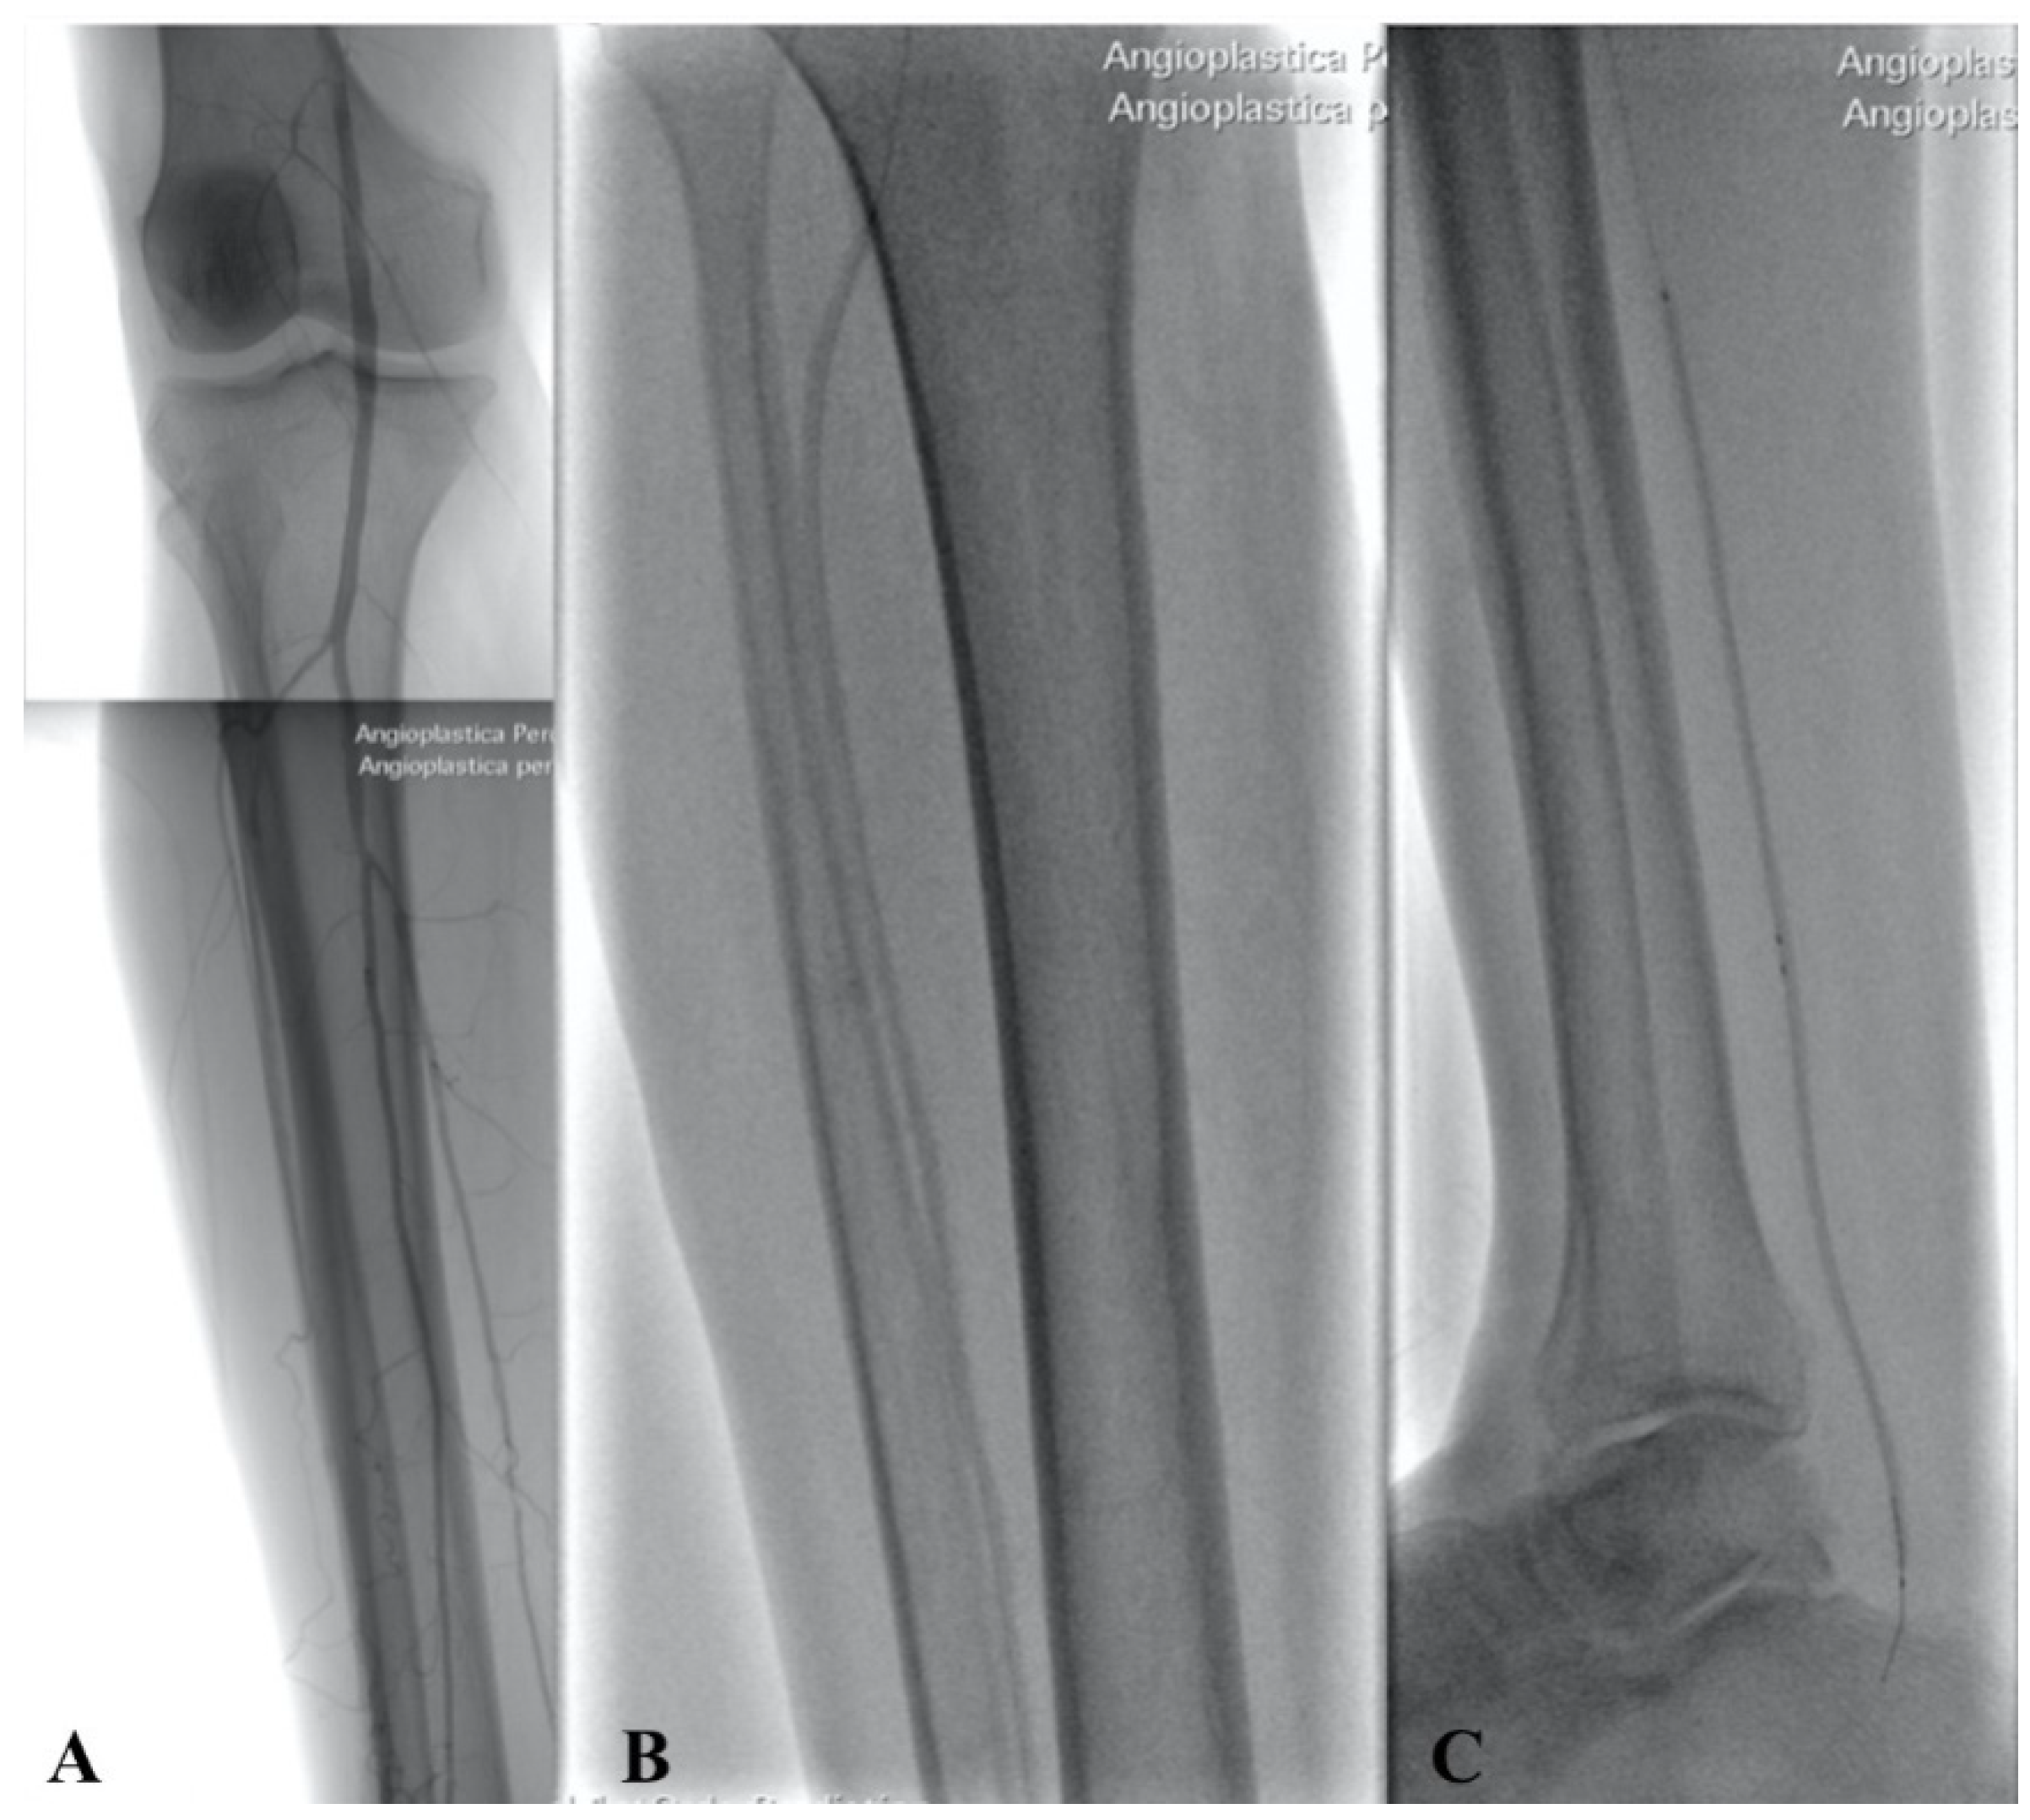

2.2. Technique